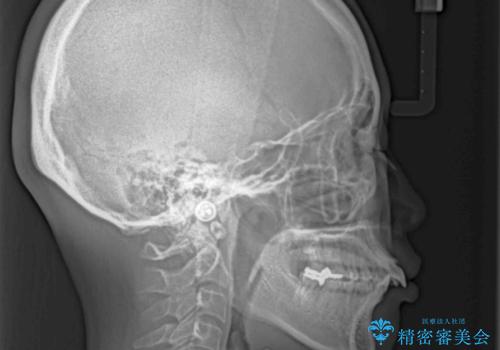

- 上の前歯が出っ歯と突出した口元を気にして来院された患者様です。

上顎歯列全体が前方に飛び出している印象であったので、上顎左右の第一小臼歯2本を抜歯し、ワイヤー装置にて抜歯矯正を行うこととしました。

骨格的に上顎が前方にあり、上顎のみの抜歯矯正のため、期間はかかることが予想されましたが、スムーズに移動してくれたおかげで、2年弱の短期間で終えることができました。